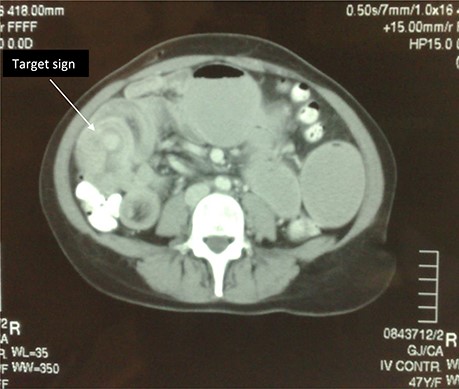

Subsequently she underwent radiological investigation of her chest and abdomen. CT abdomen revealed distension of the stomach as well as grossly distended loops of the small bowel. There was a lead point noted in the right iliac fossa with an ileoileal intussusception (Fig. 1). CT of her chest showed a large heterogeneous soft tissue density in the left upper lobe with associated left hilar and subcarinal lymphadenopathy.